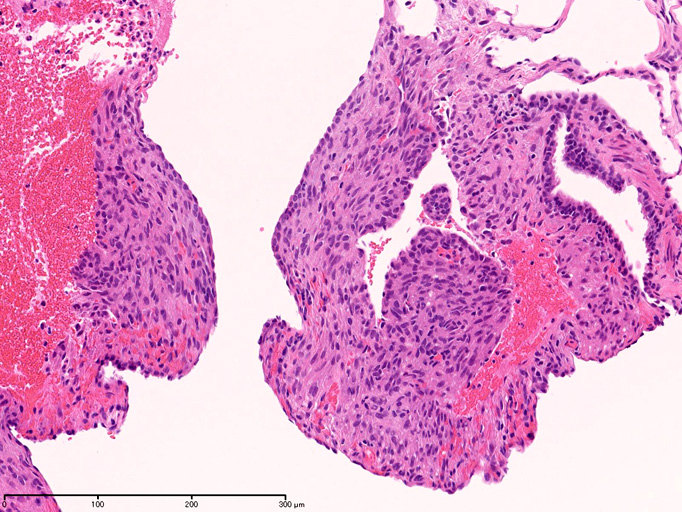

LAMの肺病変

嚢胞周囲または肺血管, リンパ管, 細気管支にそうLAM cellの浸潤, 集簇を特徴とする。LAM cellには2種類が認められ, 小型紡錘形細胞と細胞質の豊富な類上皮様細胞があり, 紡錘型は主に集簇巣の中心に存在し増殖能が高い。 類上皮様LAM cellは辺縁部に多く, 増殖能は低いがHMB45を強く発現している。

LAM cellの免疫染色--SMA, desmin, vimentin(vimentinはいつも陽性とはならない)が陽性となりmuscle lineageであるが典型的な筋細胞と異なり,

嚢胞形成はLAM cellの増殖と関連しており, 細胞が産生するmatrix metalloproteinases(MMPs)による組織破壊によるらしい。